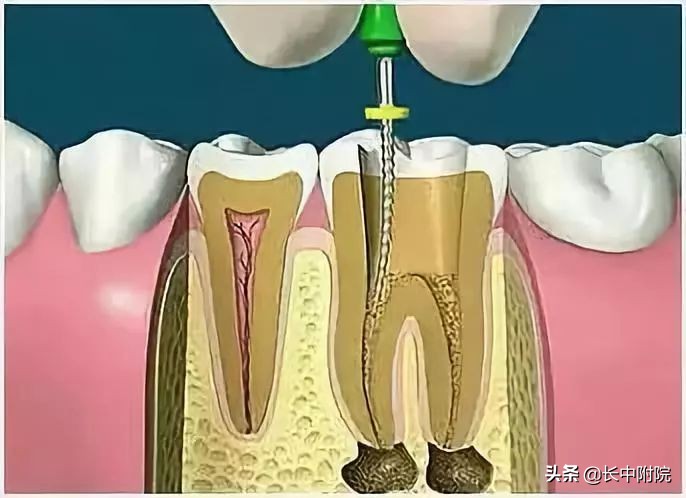

4.根管预备

根管清理成形的目的是去净根管壁上的感染物,通过根管器械的切削作用去除感染的牙本质并清理根管壁细菌以利于根管充填。

5.根管冲洗、消毒

根管冲洗的目的是清除微生物、冲掉残渣,润滑根管器械和溶解有机残渣。然后,再进行根管消毒,使根管内达到无菌状态。